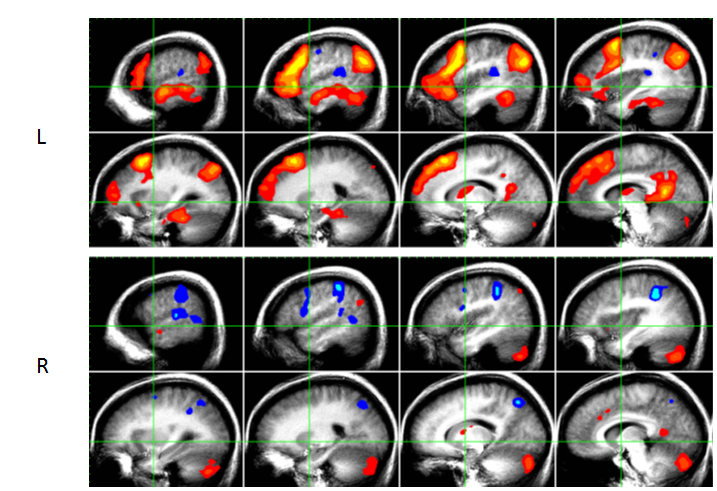

How is fMRI used to measure cerebral dominance?

A

• based on changes in the ratio of oxyhemoglobin to deoxyhemoglobin

• cognitive activity is correlated with a change in this ratio

• used to identify those brain regions activated by a given cognitive task

When conducting a fMRI study, what areas of the brain are “activated” for language?

Areas of language activation include:

1. left frontal, temporal and parietal regions

2. right cerebellum